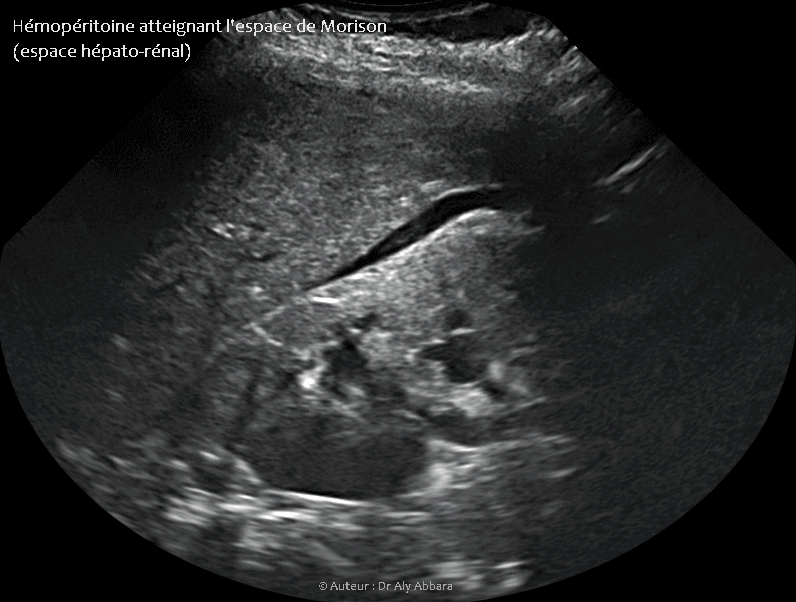

Hémopéritoine atteignant l'espace de Morison

Hémopéritoine atteignant l'espace de Morison (espace hépato-rénal)

• Images échographiques animées montrant un hémopéritoine inondant la cavité abdominale ; il est visible sur ces images au niveau du petit pelvis et au niveau de l'espace de Morison.

• En per-opératoire cette hémorragie intra-abdominale est estimée à 1 300 ml du sang ; elle est provoquée par une grossesse extra-utérine tubaire distale évolutive âgée de 9 SA et 2 jours en cours d'expulsion par un avortement tubo-abdominal.